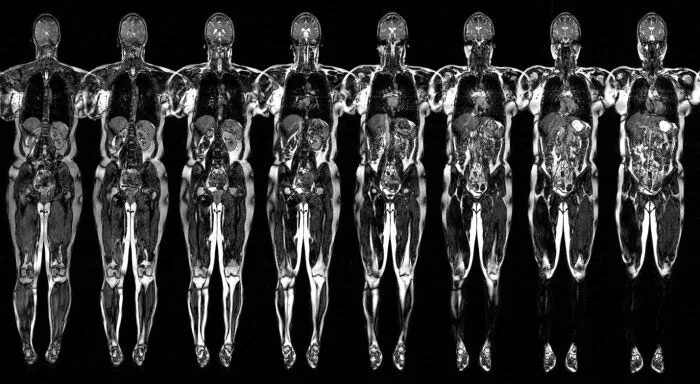

Мрт диффузия всего тела